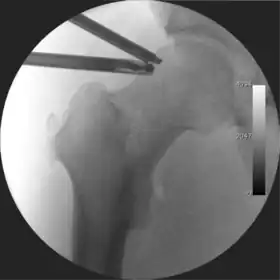

Intraoperative fluoroscopic image during an arthroscopic resection of a cam lesion of the femur. The upper instrument is the arthroscope (viewing device), while the lower is the high-speed burr used for reshaping the bone.

Standard arthroscopic treatment of symptomatic cam FAI involves debridement (resection) or repair of any labral [10] and chondral injuries [11] in the central compartment of the hip, and subsequent reshaping of the head-neck junction of the upper femur (osteochondroplasty) in the peripheral compartment [12][13] using high-speed motorised burrs that are similar in design to a dentist's drill (see fig. 9).